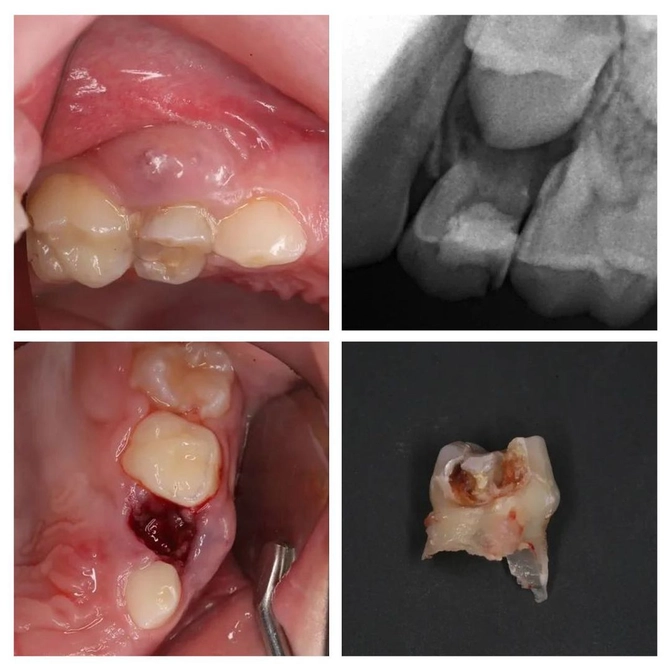

Свищ - показание к удалению молочного зуба!

Пациенту 7 лет.

Мама привела его лечить зубы, т.к. «четверка» уже сильно разрушена.

Сделали снимок и что видим: воспаление уже вышло за пределы зуба и поразило периодонт (связочный аппарат, который удерживает зуб на месте).

Это прямое показание к удалению молочного зуба!

Сразу сказала, что нужно удалять, что со дня на день на десне вылезет свищ.

Что вы думаете — СВИЩ❗

Зуб, естественно, удалили.